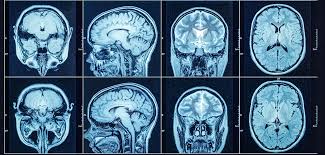

Magnetic Resonance Imaging (MRI)

Magnetic Resonance Imaging (MRI) is a medical imaging test that uses a powerful magnetic field, radio waves, and a computer to create highly detailed images of the body’s organs and tissues. Unlike X-rays or CT scans, MRI does not use ionizing radiation.

Uses powerful magnets and radio waves to produce detailed images of organs and tissues.

- Does not use ionizing radiation

- Provides detailed images of soft tissues

- Used for brain, spinal cord, and pelvic cancers